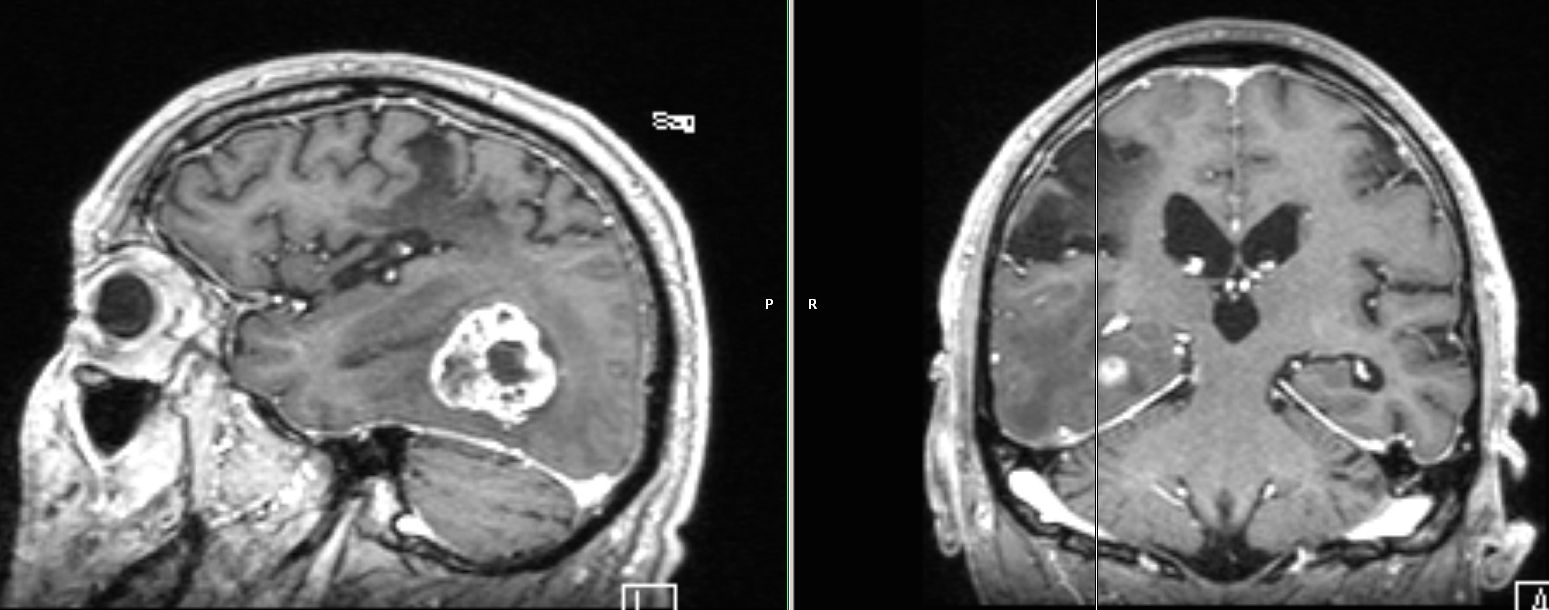

| große zystische Hirnmetastase | asymptomatisches Adenokarzinom des linken

Hauptbronchus mit primärer Hirnmetastase![]() ![]() |